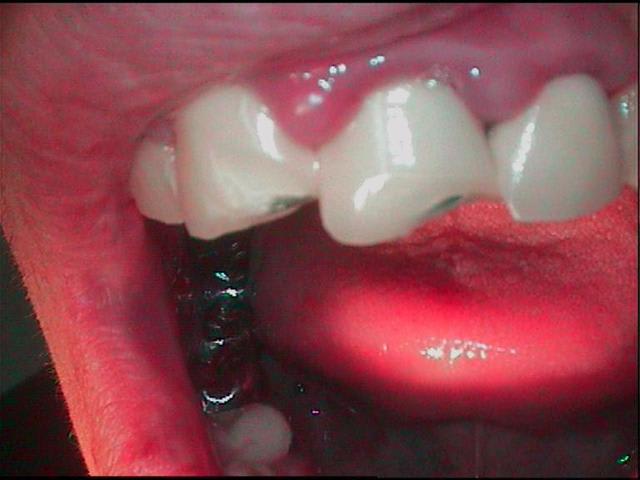

porte poisse va!!! m'en arrive un beau,accident de vtt, de plus les anterieures sont solidarisées entre elles, le gamin n'a pas un rond, il etait pas assuré,et les muqueuses saignent des qu'on les regarde, et il est malheureux comme les pierres...et bien sur....il n'a pas de dentiste...

gamin avec des CCM sur les antérieures ?

ET des molaires bien blindees

pfff...23 ans...bin oui quoi gamin!!!! qui fait le fou en vtt casquette en arriere, pas assuré, sans job, chez papa et maman, qui veut plaire aux boutonneuses et qu'est pas en bonne passe...

le verrai lundi soir en quinze, ferai des photos du visage, verrez bien...gamin gamin gamin!!!

oui bin plus tard!!! veux bien rendre service mais faut aussi que je survive dans ce monde brutal, alors photo pour montrer que c'est un gamin quand meme...

le 22 mai,reception d'une photo d'un gamin

*est ce la photo de ton patient?

*dans ce cas,pourquoi ce rendez vous précipité?

*l'as tu convoqué pour prendre la photo pour satisfaire notre curiosité?

*si c'est lui,comment se fait il que tu n'aies pu

simple, me suis gourré, c'etait aujourd'hui, pas la semaine prochaine, j'étais le premier étonné de le voir fleurir aujourd'hui